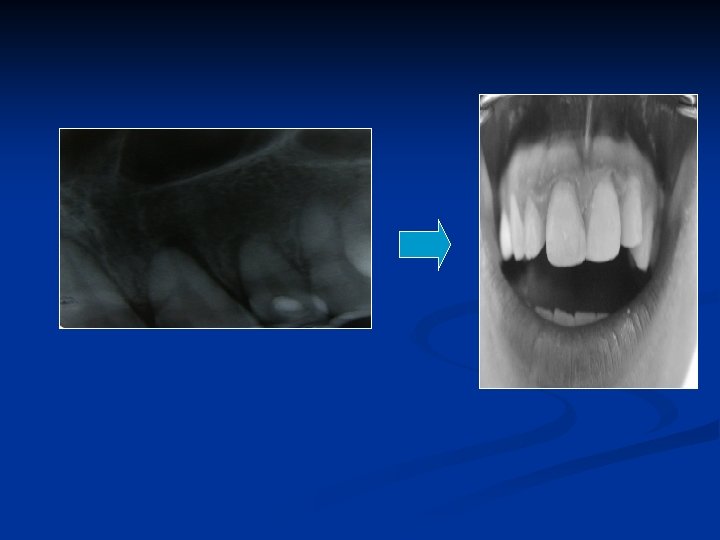

İNTERNAL –EKSTERNAL REZORBSİYON ? ? ? Bite-wing radyografisi

İNTERNAL –EKSTERNAL REZORBSİYON ? ? ? Bite-wing radyografisi Periapikal radyografisi

İNTERNAL –EKSTERNAL REZORBSİYON ? ? ? Bite-wing radyografisi Farklı açıdan alınmış periapikal radyografisi Periapikal radyografisi

İNTERNAL –EKSTERNAL REZORBSİYON ? ? ? Bite-wing radyografisi Farklı açıdan alınmış periapikal radyografisi Periapikal radyografisi 1 yıl önceki